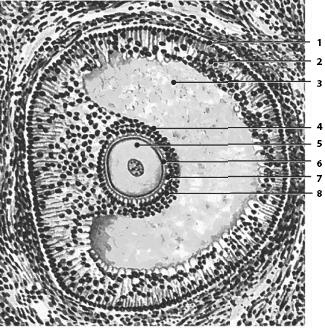

Рис. 54. Строение пузырчатого (везикулярного) фолликула яичника (граафова пузырька). 1 – наружная оболочка фолликула; 2 – внутренняя оболочка фолликула; 3 – полость фолликула с фолликулярной жидкостью; 4 – яйценосный холмик; 5 – яйцеклетка; 6 – блестящая оболочка; 7 – лучистый венец; 8 – фолликулярные клетки

Яйцеклетка человека относится к олиголецитальным (маложелтковым) вторичным с равномерным распределением желточных включений (изолецитальные). Яйцеклетка покрыта блестящей оболочкой, которая окружена слоем питающих их фолликулярных клеток, вырабатывающих женские половые гормоны, выполняющих по отношению к ооциту трофическую, защитную и барьерную функции. Яйцеклетка, окруженная одним слоем фолликулярных клеток, оттесняется к одному из полюсов фолликула (яйценосный холмик), образуя быстро увеличивающуюся в размерах полость – граафов пузырек (рис. 54). Он разрывается, и яйцеклетка (овоцит первого порядка, окруженный блестящей оболочкой и 3–4 тыс. фолликулярных клеток) выходит в свободную брюшную полость, откуда попадает в маточную трубу, где и созревает. Во время созревания клетка претерпевает два митотических деления, в результате чего последовательно образуются овоцит второго прядка зрелая яйцеклетка, обладающая, как и сперматозоид, гаплоидным набором хромосом.

В течение жизни женщины лишь 400–500 первичных фолликулов преобразуются в зрелые везикулярные фолликулы яичника (граафовы пузырьки) в результате сложных процессов овогенеза, которые происходят циклически каждые 28 дней. При этом первичный фолликул растет, в нем интенсивно размножаются клетки фолликулярного эпителия. Он становится цилиндрическим, многослойным, вокруг развивается тека фолликула (соединительнотканная оболочка), фолликулярные клетки начинают вырабатывать жидкость фолликула, содержащую гормоны эстрогены, которая раздвигает их. Одновременно растет и ооцит первого порядка, вокруг него образуется блестящая оболочка.